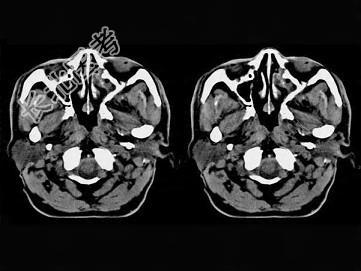

- 单项选择题男,61岁, 流鼻血三天。如图所示最可能的诊断为 ( )

A、鼻咽淋巴滤泡增生

B、鼻咽腺样体增生

C、鼻咽纤维血管瘤

D、小唾液腺瘤

E、鼻咽部息肉